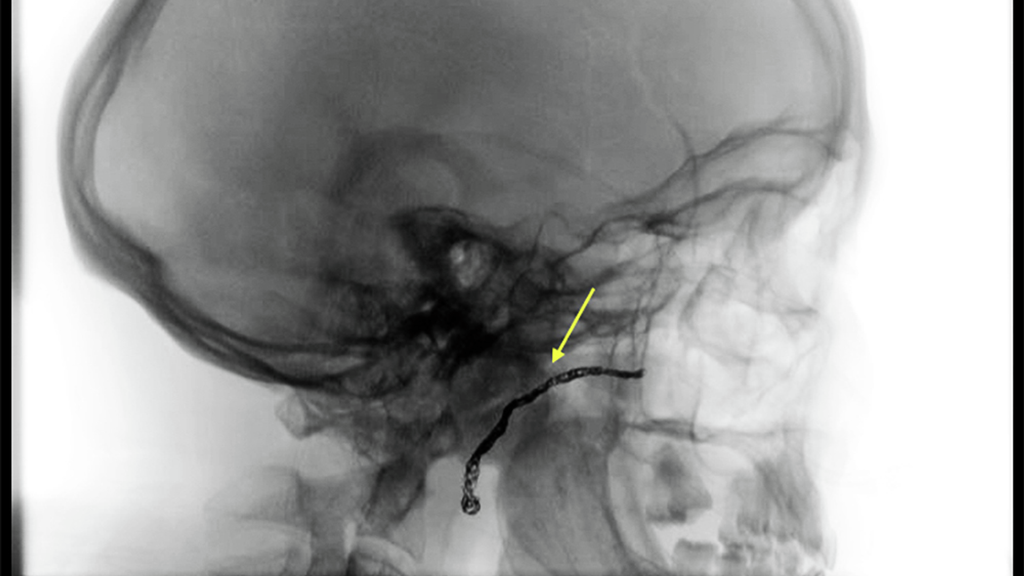

CT scans showing TMJ bony growth (ankylosis) and jaw fusion before TMJ replacement surgery (A) and after resection of bony mass and TMJ replacement (B)

Figure 2: A. Preoperative coronal CT showing massive TMJ ankylosis and fusion of the mandible to the skull base. B. Postoperative coronal CT following ankylosis resection and immediate temporomandibular joint replacement. Note arrow showing the embolized internal maxillary artery.

Following a CT angiogram, massive ankyloses was evident along with intimate involvement of the internal maxillary artery. Virtual surgical – planning was performed in order to design the bone cuts to ensure adequate bone removal along with avoidance of the middle cranial fossa, external auditory canal, and inferior alveolar nerve.

At his scheduled surgery, the bone resection occurred as planned and a stock TMJ Biomet prosthesis was placed (Figure 2B). Mr. W started immediate function using the TMJ enhanced recovery after surgery (ERAS) protocol and was discharged the following day.